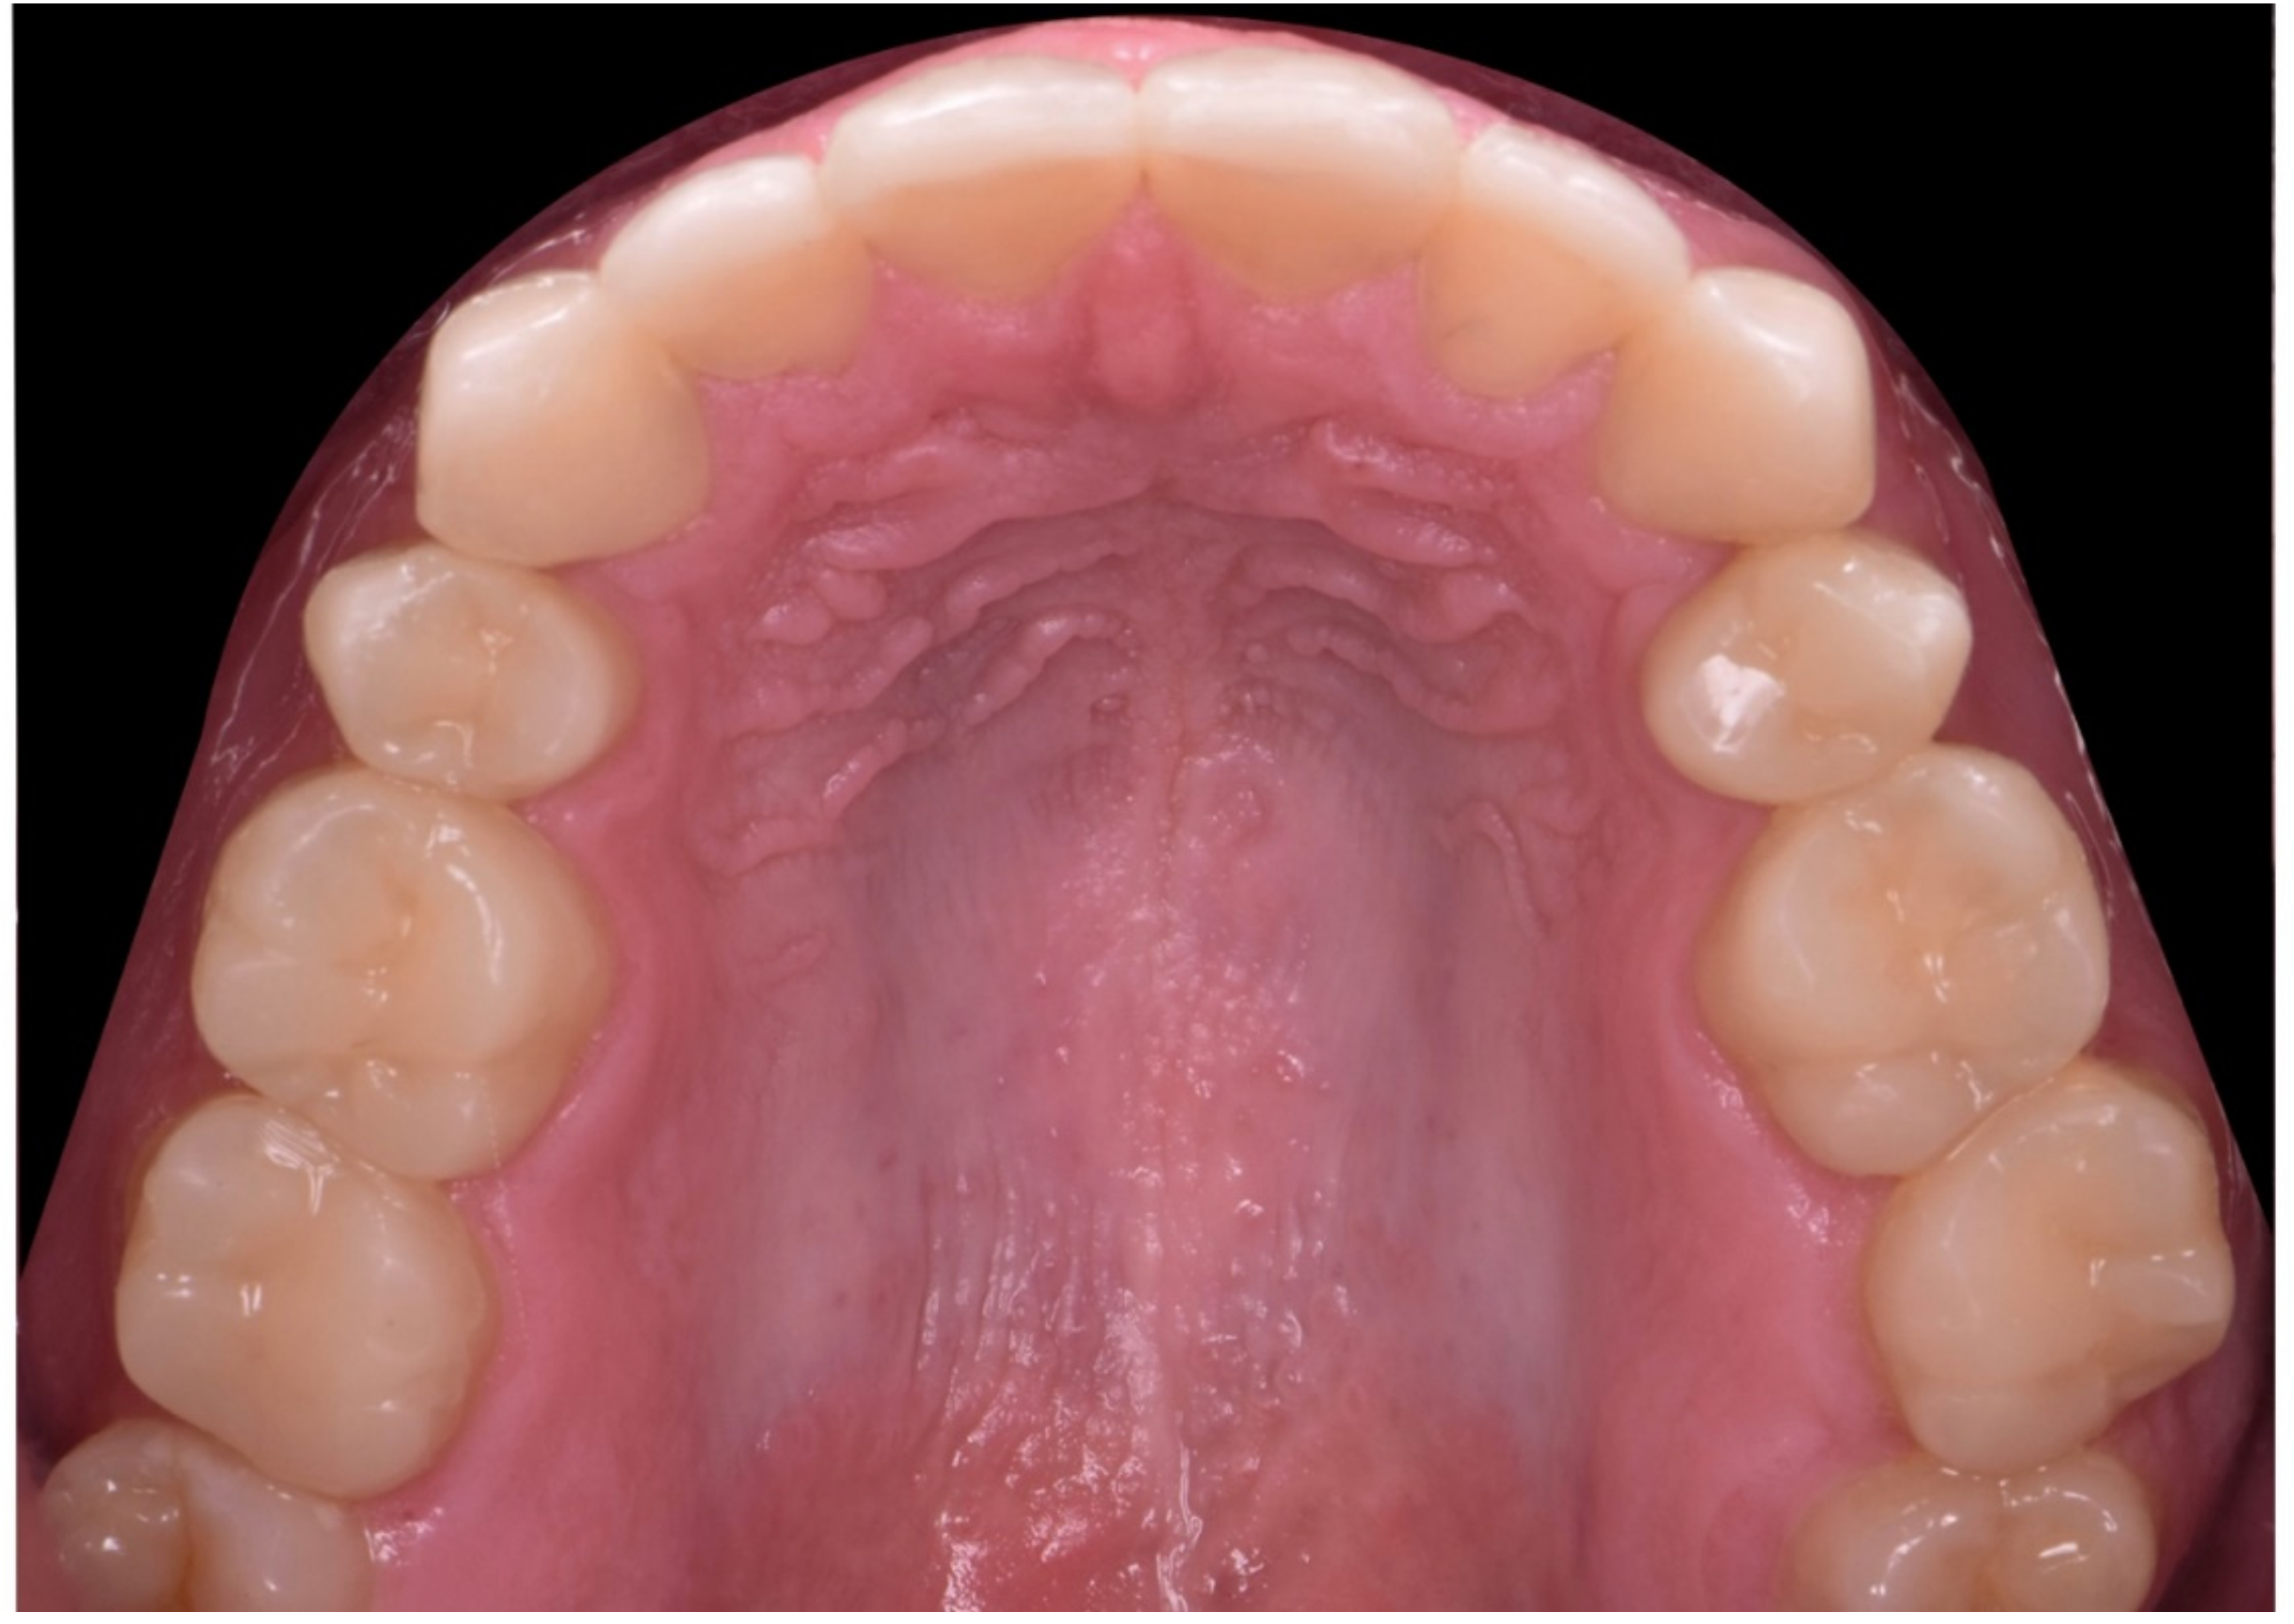

2. Clinical Report

2.1. Planning Phase